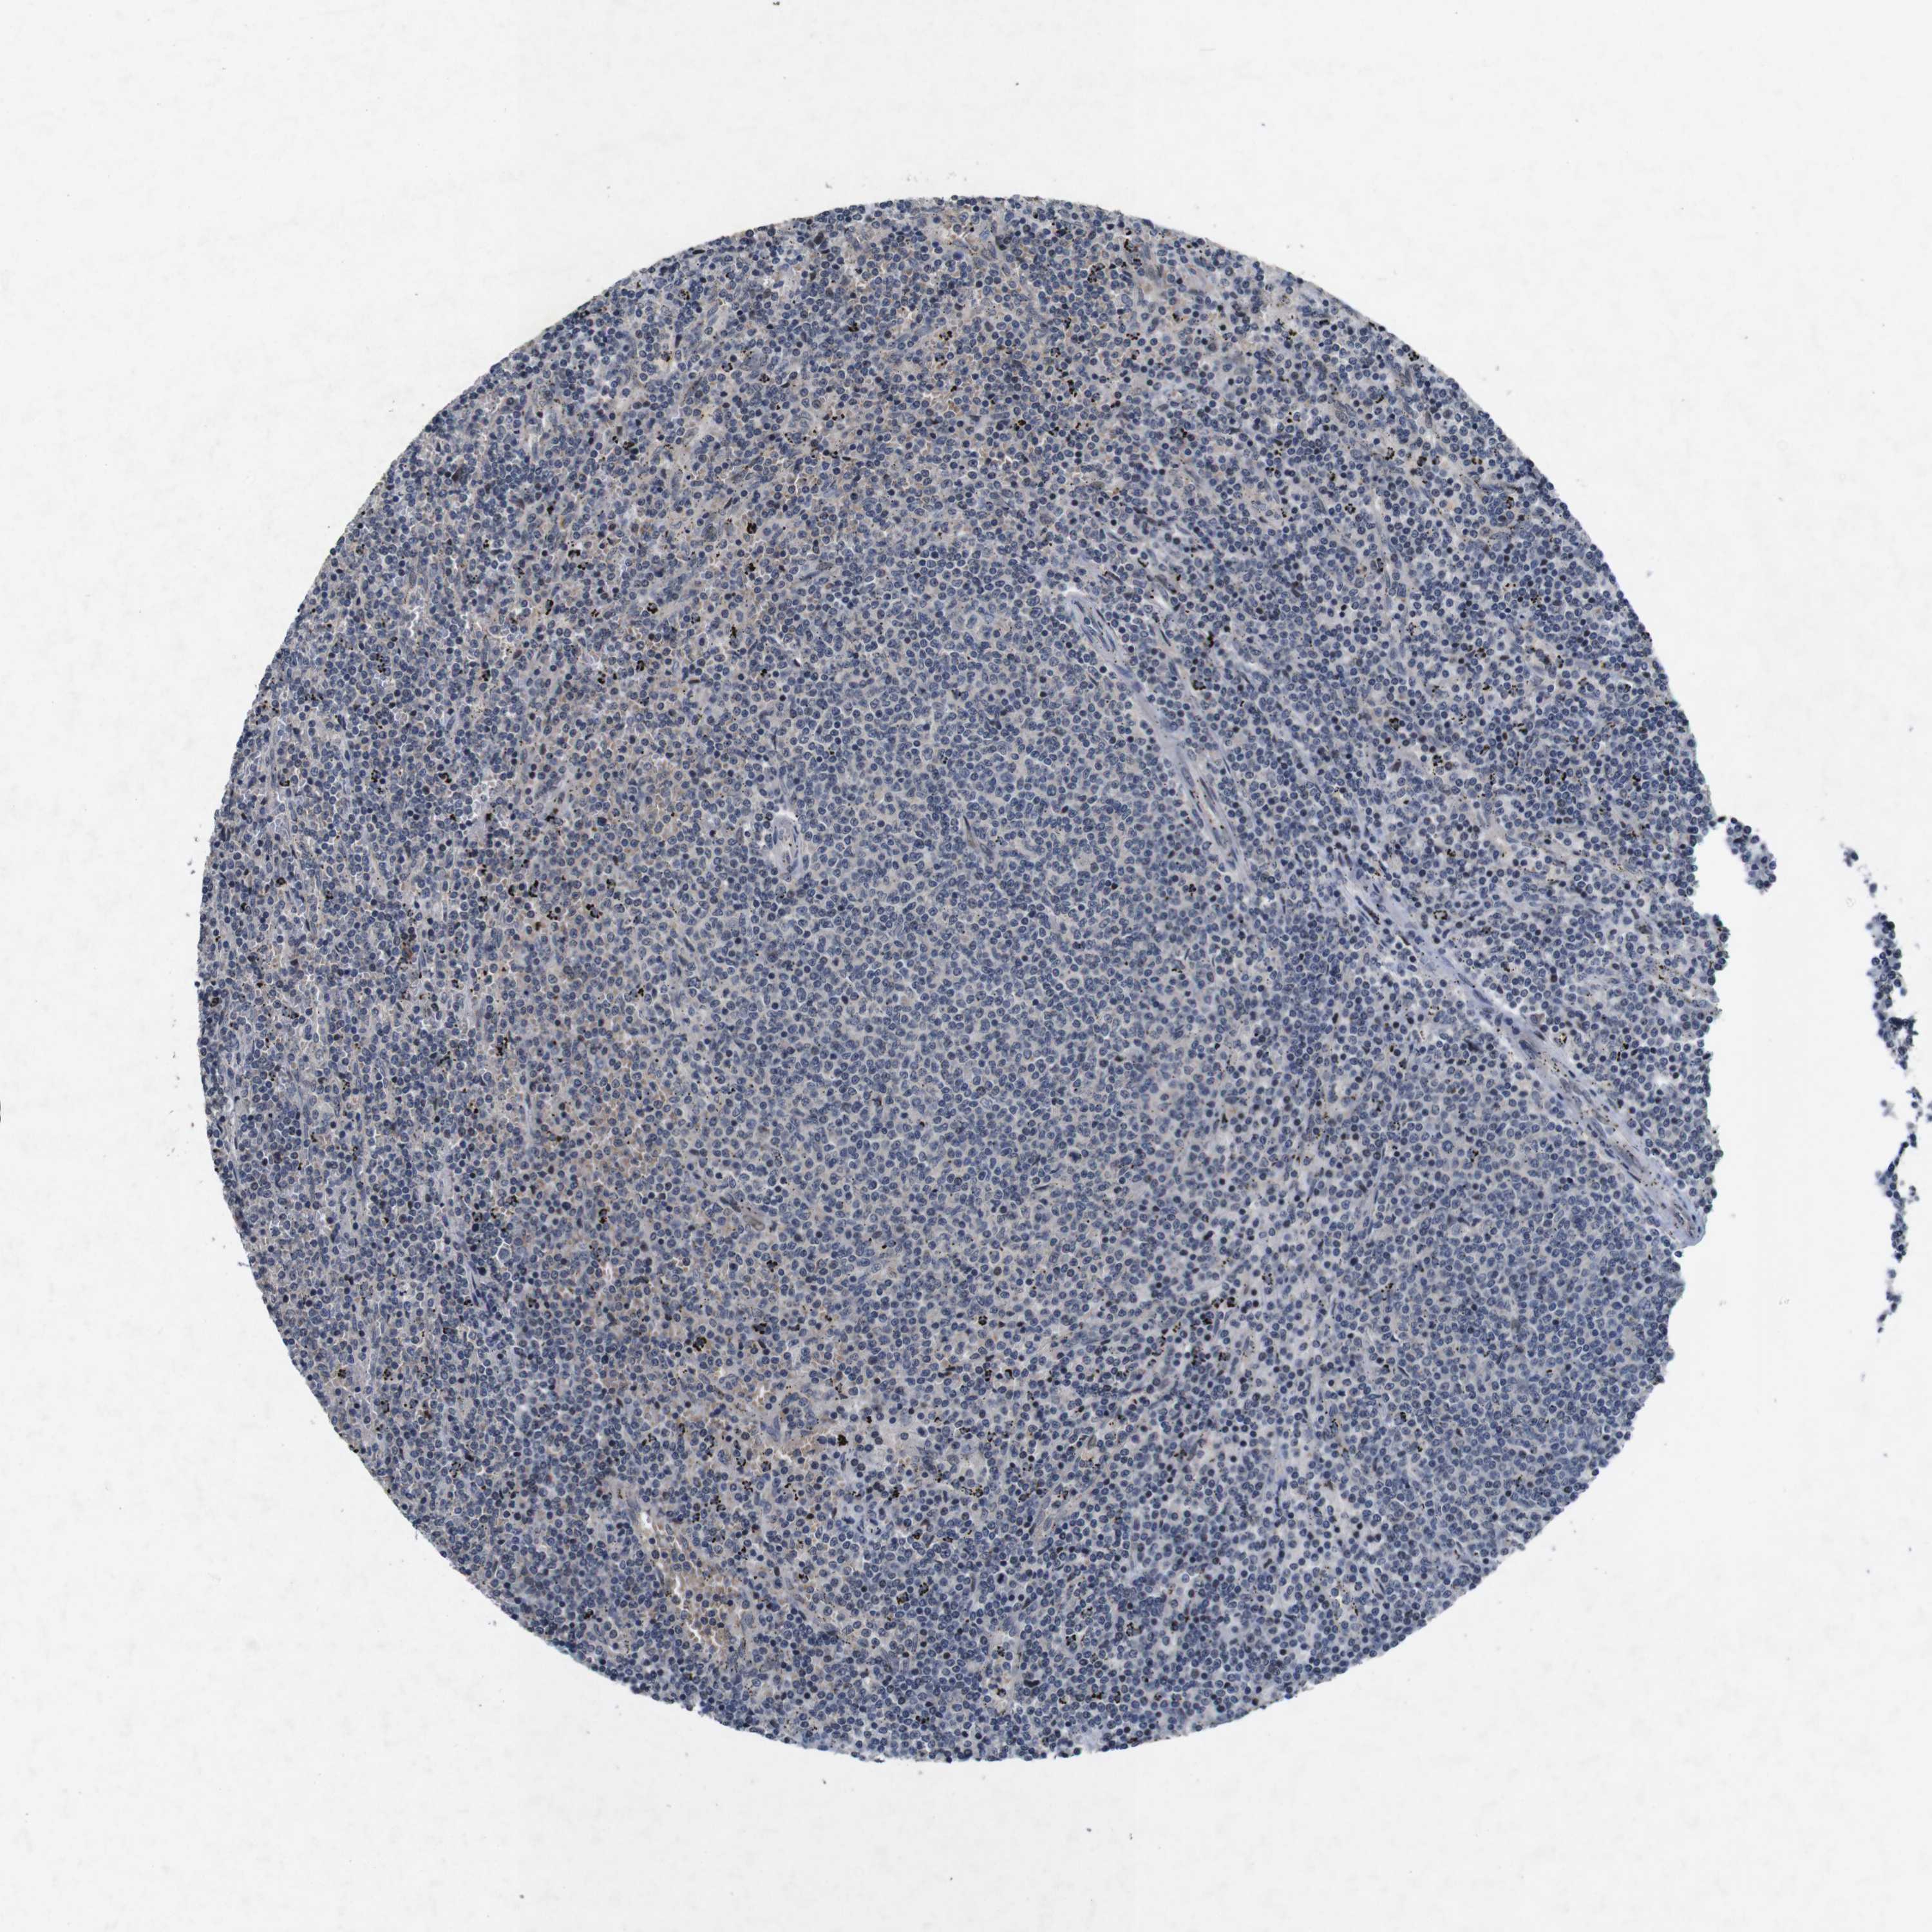

CANCER LYMPHOMA Show tissue menu

LYMPHOMA - Protein expressioni

A mouse-over function shows sample information and annotation data. Click on an image to view it in a full screen mode. Samples can be filtered based on level of antibody staining by selecting one or several of the following categories: high, medium, low and not detected. The assay and annotation is described here.

Antibody stainingi

Antibody staining in the annotated cell types in the current human tissue is reported as not detected, low, medium, or high, based on conventional immunohistochemistry profiling in selected tissues. This score is based on the combination of the staining intensity and fraction of stained cells.

Each image is clickable and will lead to virtual microscopy that enables deeper exploration of all samples and also displays staining intensity scores, fraction scores and subcellular localization as well as patient and tissue information for each sample.

Antibody HPA026441

Antibody CAB013090

Staining

High

Medium

Low

Not detected

Intensity

Strong

Moderate

Weak

Negative

Quantity

>75%

75%-25%

<25%

None

Location

Nuclear

Cytoplasmic/membranous

Cytoplasmic/membranous,nuclear

Hodgkin's disease, NOS

Malignant lymphoma, non-Hodgkin's type, High grade

Malignant lymphoma, non-Hodgkin's type, Low grade